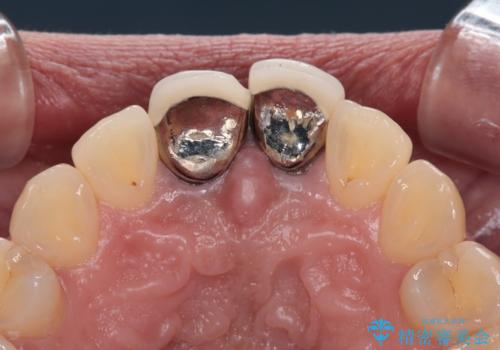

- 前歯のクラウン付近の歯肉が黒く見えることを気にして来院された患者様です。

10年以上前に根管治療を行っており、その際にはラバーダムを使用してしっかりと治療を行っていたとのことで、今回は根管治療は行わずに土台のみを作り替えた上で、オールセラミッククラウンにて補綴治療を行うこととしました。